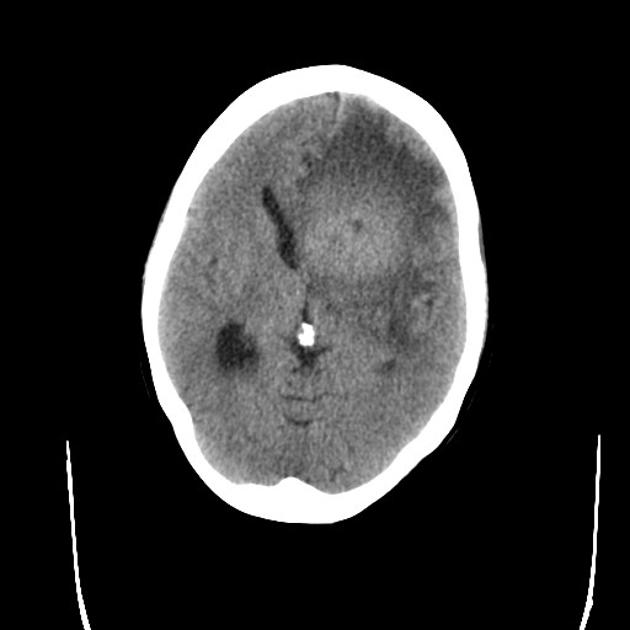

A detailed history and physical evaluation with particular attention to time course and nature of symptoms, followed by an MRI of the brain is the usual initial workup. The T1 MRI shows a hypointense or isointense lesion, and T2/FLAIR shows variable surrounding edema. T1/Gad shows homogenous enhancement without ring enhancement and lacking central necrosis. Ring enhancement occurs more often in immunocompromised patients.

CT images are hypointense. Hemorrhage is uncommon. Multiple lesions are more common in HIV+ patients.